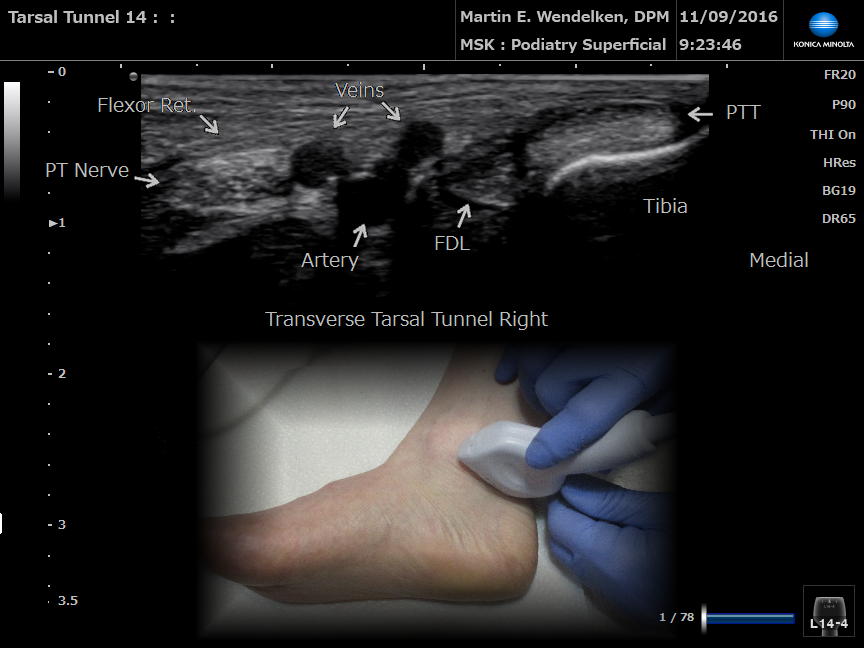

• Image 8: Transverse 1st MPJ